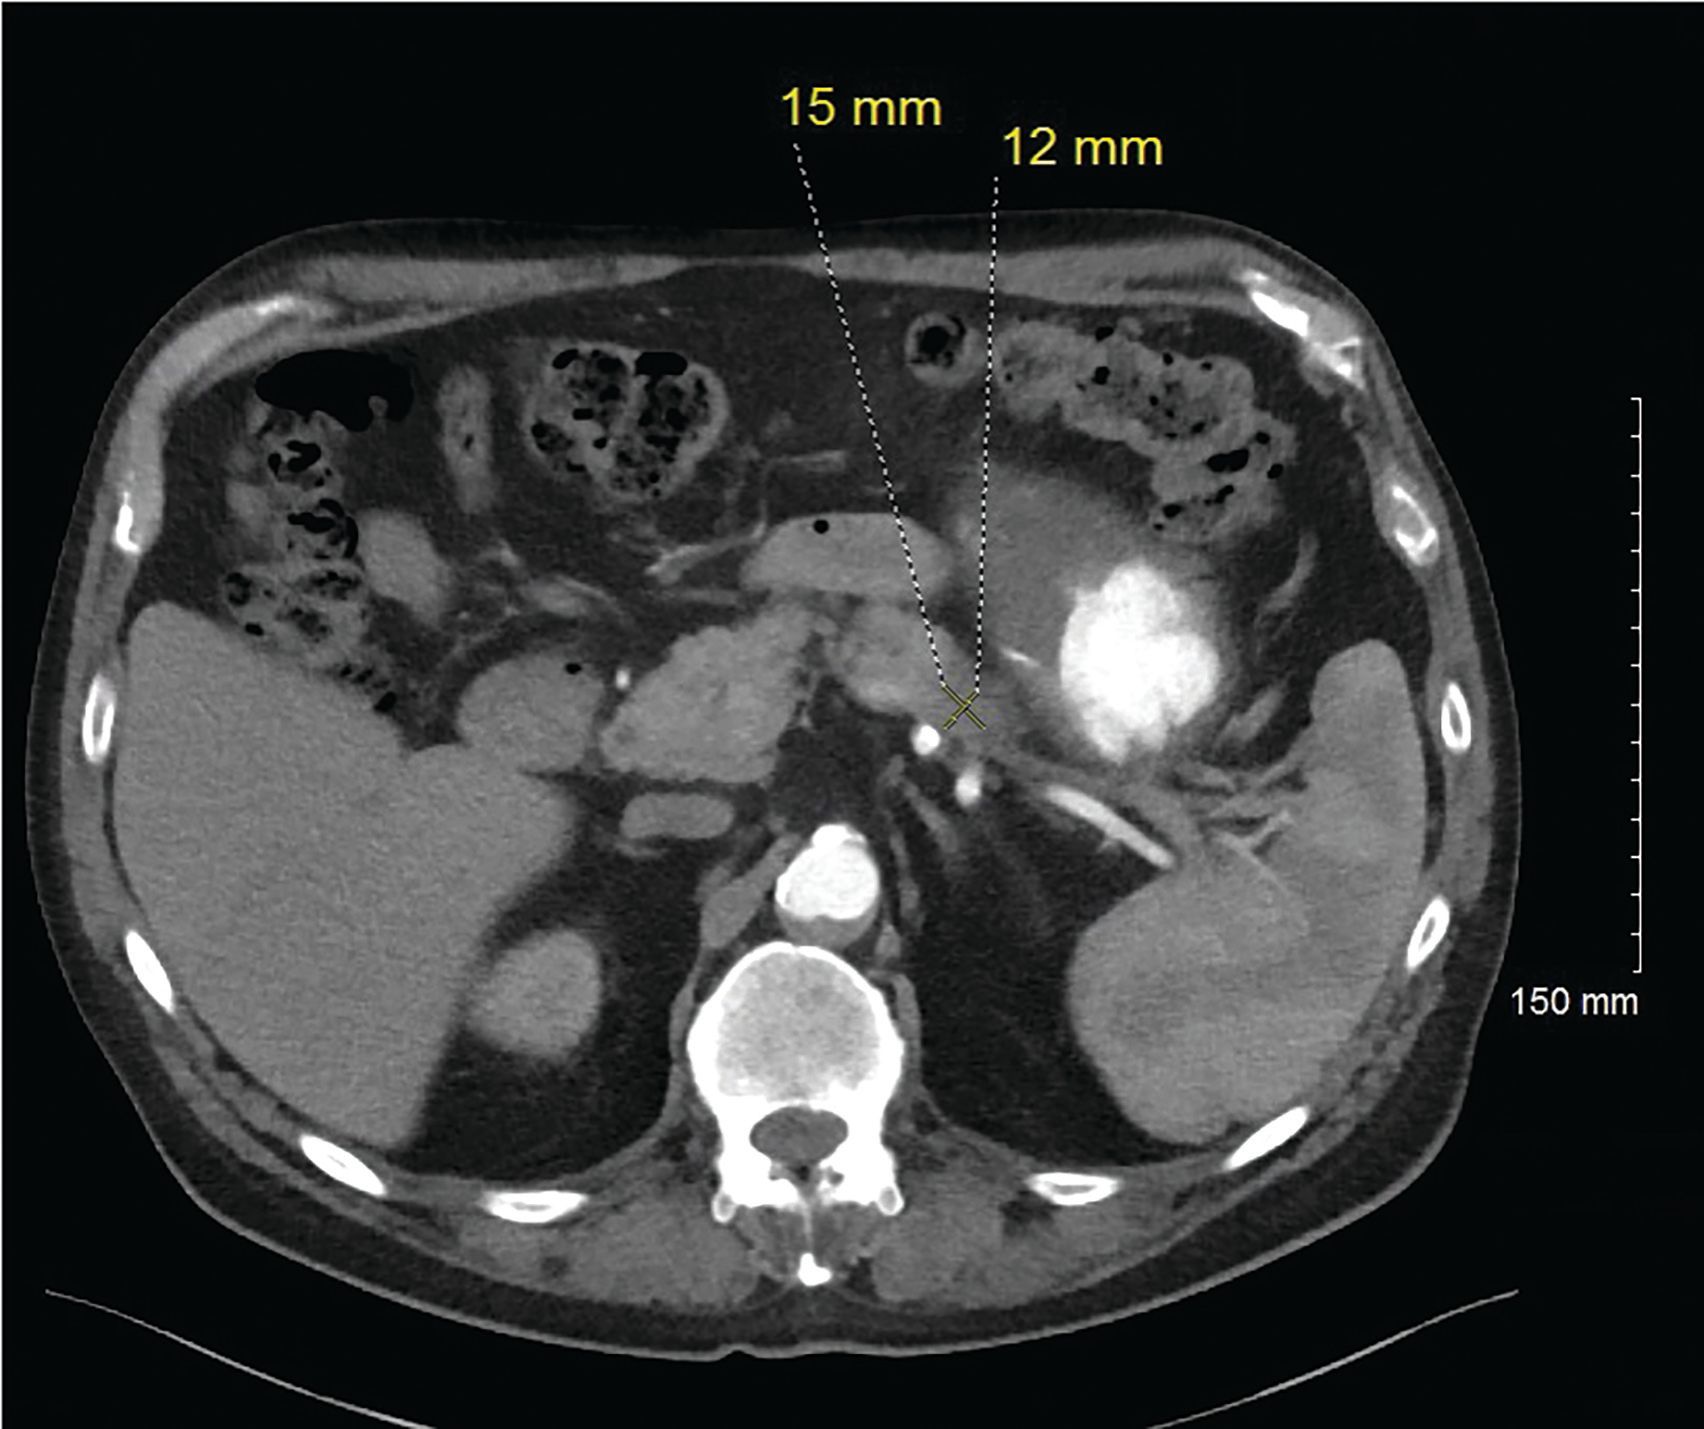

Figure 3. 12/6/19. Axial contrast enhanced CT (arterial phase) again demonstrates the subtle hypoenhancing lesion in the pancreatic tail. Decreased from 34 x 25 mm to 15 x12 mm.

For his newly diagnosed locally advanced PDAC, the patient was treated with 6 cycles of a neoadjuvant FOLFIRINOX chemotherapy regimen, which reduced his pancreatic mass from 3.4 cm x 2.5 cm to 1.5 cm x 1.2 cm on imaging studies (Figure 3). He underwent a successful partial pancreatic body/tail pancreatectomy and splenectomy. Pathology revealed a 2.4-cm (pT2) residual invasive moderately differentiated PDAC arising in association with a low-grade intraductal papillary mucinous tumor at the proximal margin. While there was some perineal invasion, there was no lymphovascular invasion or any involved lymph nodes, of 14 removed (pN0). All resection margins were negative (R0 resection) (Figures 4, 5, 6). Spleen was without diagnostic abnormality. Immunostaining for DNA mismatch repair proteins (MLH1, MSH2, MSH6, and PMS2) revealed retained nuclear staining for all 4 antigens. Results of the next-generation sequencing of tumor tissue revealed a microsatellite-stable tumor with a tumor mutational burden of 3 mutations per megabase. Genomic findings showed CDKN2A/B loss and presence of KRAS-Q61H, SGK1-K138fs13, SMAD4-P18fs17, and TP53-R273H, with no reportable therapeutic or clinical trial options.